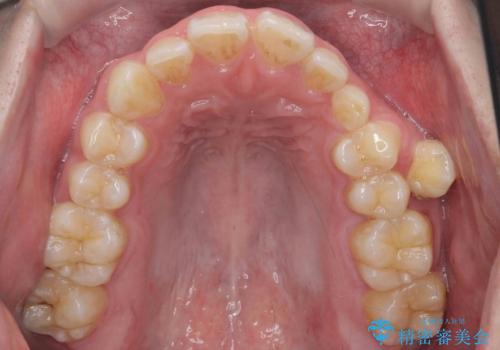

左上の乳犬歯が残っており、その下から生えてくるはずの犬歯(永久歯)が左上小臼歯部に萌出していました。

左上の乳犬歯は根もしっかりしていたため、

➀そのまま矯正する。乳歯がいずれダメになったときにそこはブリッジかインプラントを検討する

②乳歯は抜歯し、ブリッジかインプラントを矯正後に入れる

を提案し、➀を選択されました。

将来的にインプラントは希望されないとのことだったため、乳歯の部分は隙間を開けてインプラントを入れる用のすき間を確保するということは特に行いませんでした。

乳歯をそのまま並べたため、上顎の左右の犬歯の幅は非対称になっています。